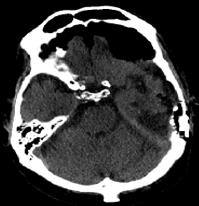

Post Traumatic Tension Pneumocephalus Ct Findings Eurorad